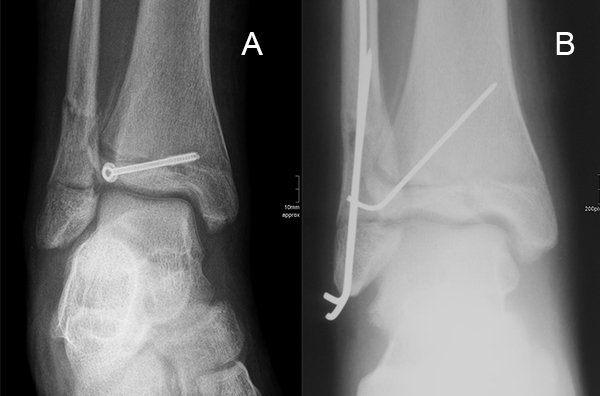

Ist die korrekte Stellung nur gegen einen federnden Widerstand zu erreichen, kann die Fraktur durch perkutane K-Drähte stabilisiert werden. Bei einer Fugenschaftfraktur mit großem Keil ist auch eine Schraubenosteosynthese möglich (Abbildungen 13 bis 14).

Dislozierte Frakturen (Frakturspalt > 2 mm) werden grundsätzlich operativ behandelt. Die Reposition kann arthroskopisch unterstützt erfolgen. Die Schraubenosteosynthese erfolgt entsprechend dem Frakturverlauf. Bei Twoplain Frakturen ist meist eine epiphysäre Schraube ausreichend die von lateral kommend das Fragment nach medial-proximal fixiert. Der Schraubenverlauf ist üblicherweise von lateral ventral nach proximal dorsal medial (Abb. 24). Nach Reposition darf in der seitlichen Aufnahme des Sprunggelenks, als auch in der 45° Außenrotationsaufnahme keine Stufe in Höhe der Wachstumsfuge erkennbar sein. Eine sichtbare Stufe ist Indikator für eine unzureichende Reposition.

Bei Triplane-Frakturen fasst die metaphysäre Schraube das metaphysäre Fragment einschließlich eines hinteren Volkmann Dreiecks, die epiphysäre Schraube fasst das epiphysäre Fragment. Da der Fugenschluss noch nicht abgeschlossen ist, sollten die Schrauben die Wachstumsfuge nicht kreuzen, obwohl eine Wachstumsstörung unwahrscheinlich ist (v. Laer 2013).